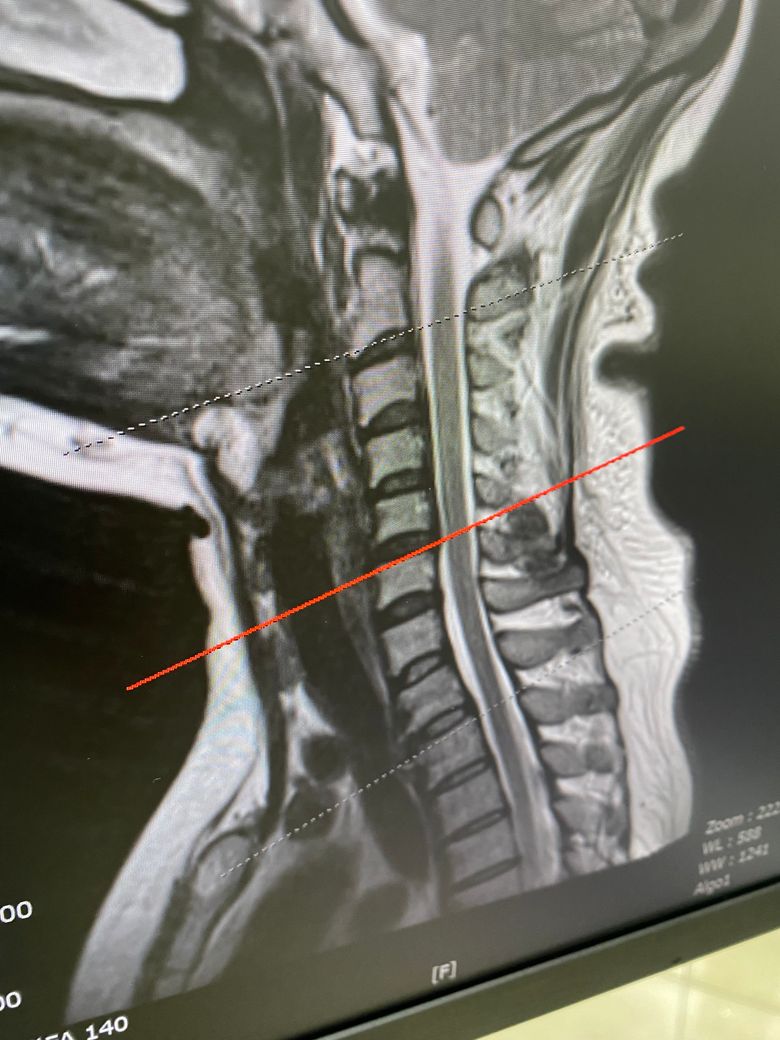

MRI 사진인데... 현재

한달전 쯤 찍은 사진이고

첫번째 사진만 보여주셔서 심각성을 크게 잘 몰랐는데

• 1번 째 사진

목에 있는 추간판의 팽윤이 보이는 것 같습니다.

사실 여러 환자분들 보았지만, 그렇게 심하진 않습니다. 병원에서는 현상 상태를 말하니 디스크라는 표현에 환자분들이 걱정을 많이 하는데, 지금 그렇게 심해보이진 않습니다. 그리고 신전운동 할때 뻐근한거는 제 생각인데 목이 구조가 현재 일자목인데, 등도 좋아보이지 않습니다. 등도 굽어계시거나 평평하게 일자로 되있으실거같은데, 그런 목 등 에 대한 움직임 개선이 좋아 보일거같지 않습니다.

일자목에 약간의 역c커브형태로 보여집니다 맥킨지 신전자체가 찌릿하거나 불편함이 가중되면 일단 중지하시는게 좋고, 약물치료와 더불어서 운동치료 가능한 병원 가셔서 운동도 같이 해보시는게 좋겠습니다. 견갑 위주의 운동 + 맥킨지 운동을 각도를 줄여서 한다거나 하는 식의 변형이 도움이 되겠습니다

• 올리신 사진 세 장만 가지고 정확하게 어떻다 이야기 하기는 어렵습니다만, 디스크가 명확하게 돌출이 되어 있기는 하지만 신경을 누르는 정도가 딱히 심해 보이지 않습니다. 해당 사진들만 보았을 때에는 심각한 수준의 디스크로 보이지는 않습니다.